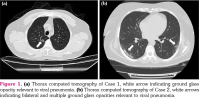

Case 1- A 47-year-old male patient with AS applied to the emergency service with the symptoms of fever, shortness of breath and non- productive cough. He had been on etanercept treatment for three years. He had no other known comorbidities. Even though the polymerase chain reaction (PCR) test for SARS-CoV-2 was found negative, he was diagnosed as COVID-19 due to thorax computed tomography (CT) signs relevant to viral pneumonia (Figure 1a). Hydroxychloroquine and azithromycin were started. Patient’s baseline high C-reactive protein (65.5 mg/L) was the only laboratory test related with poor prognosis. Thereafter, he was discharged with full recovery at the fifth day of hospitalization.